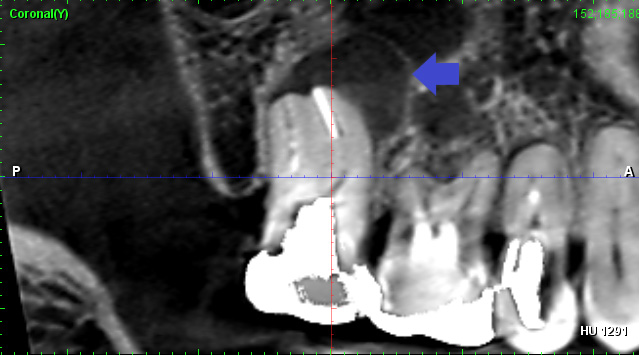

歯根の先に大きな膿があり、再根管治療が必要ですが破折ファイルが根管を塞いでいます。根管治療で膿を改善するためには、破折ファイルを除去し根管の殺菌・消毒が必要です。破折ファイルは除去が難しいケースもあり、必要に応じて外科的歯内療法を選択することもあります。本ケースは、手術なしで破折ファイルを除去し、再根管治療により大きな膿を改善しました。

破折ファイルがあり、根の先に膿がみられる場合は破折ファイル除去が必要になります。破折フィル除去には歯科用顕微鏡とCTスキャンがあると、安全にかつ確実な除去をしやすくなります。